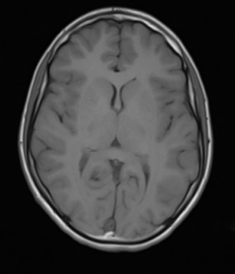

What type of clinical imaging has been used in this case?

X-ray

CT

MRI T1

MRI T2

Ultrasound

A

T2 is generally the more commonly used, but T1 can be used as a reference for anatomical structures or to distinguish between fat vs. water bright signals.

T2 – TWO tissues are bright: fat and water (WW2 – Water is White in T2)